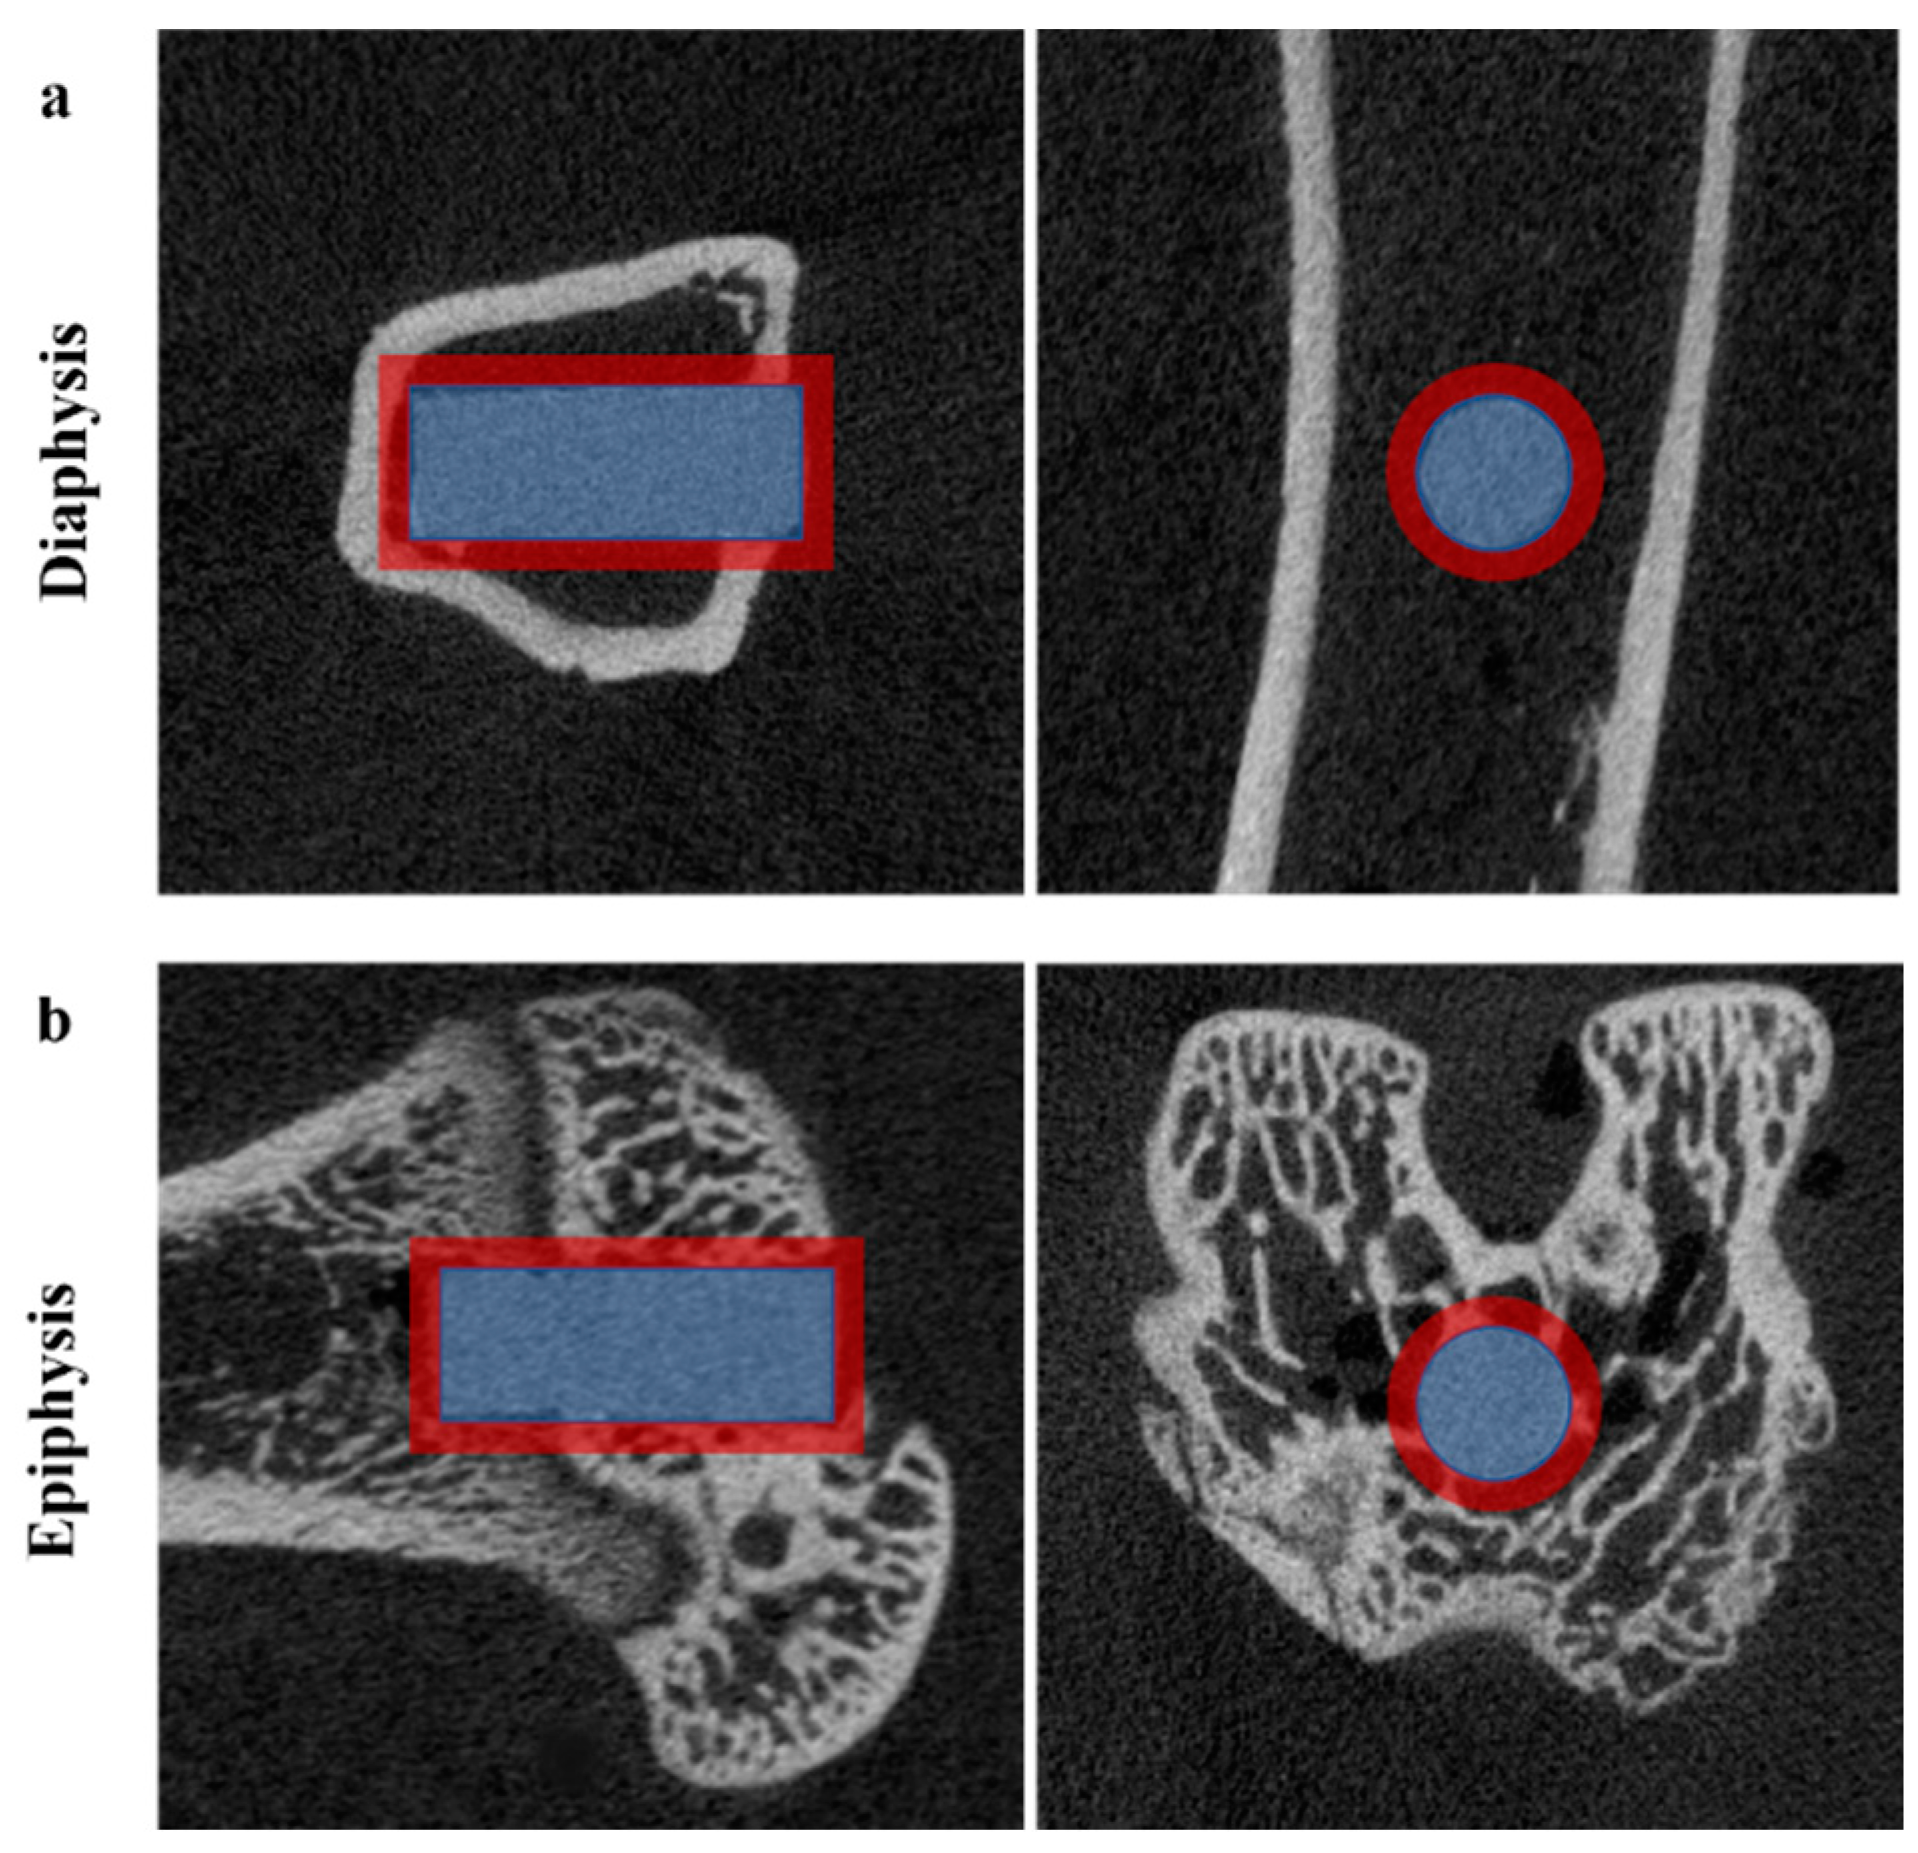

A trans-axial cutting 0.5 cm above and below the implantation point was used to harvest the bone specimens, together with the magnesium rods. Block biopsy specimens were quantitatively analyzed using A SKYSCAN 1076 Micro-CT unit (Kontich, Belgium) at 100 kV and 100 μA, with 240 ms of exposure time. The specimens were immersed in a 10% neutral buffer formalin solution during imaging. The phantom in Hounsfield Units (HU) using CTAn software version 1.16.4.1 (Skyscan) was used to estimate the bone and gas formation volumes. The micro-CT scan image was reconstructed by DataViewer software version 1.5.2.4 and then analyzed with CTAn software. A worldwide thresholding calculation was connected at a consistent edge for all examples. The region of interest (ROI), commonly defined as adjacent to the implant and endo-cortical surface for trabecular bone, specifies the area to be evaluated from the reconstructed images. The ROI for analyzing material degradation was a cylinder of the same size and position as the rod. A new larger ROI in the same shape and position was used to monitor new bone development and assess the stimulatory effects of magnesium alloys on bone growth (Figure 2). Bone volume fraction (BV/TV) is the volume of mineralized bone within a specific tissue volume of interest. Gas volume was measured in the same manner as the bone volume, but the bone mineral density (BMD) calibration value was different.

Figure 2.

The region of interest (ROI) determines the volume of the Mg rod (blue cylinder) and new bone volume (red annular cylinder). The images from the micro-CT scan were analyzed by CTAn software in the axial and sagittal planes of the Mg implantations in (a) the tibial diaphysis and (b) distal femoral epiphysis.